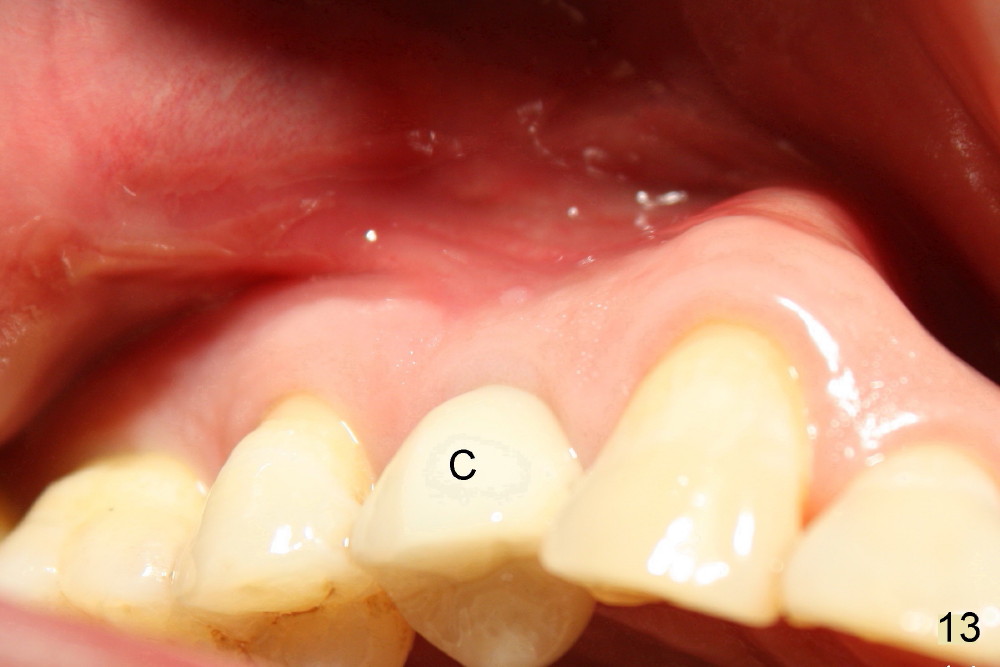

The patient returns 6 months postop for impression of a permanent restoration. The gingiva with knife-edged papillae adapts to the provisional (Fig.7). The gingiva looks healthy when the provisional is removed (Fig.8). The buccal bone resorption seems to be minimal, as compared to Fig.1,2. There is no bone loss between immediately postop (Fig.9 I; implant), 4.5 months postop (Fig.10 A: abutment), 4 and 7 months post cementation (Fig.11,12 C: crown). Soft and hard tissue morphology remains normal 7 months post cementation (Fig.13). No bone loss is observed 15 months post cementation (Fig.14). The papillae (Fig.15) and bone (Fig.16,17) remain stable 29 months post cementation.